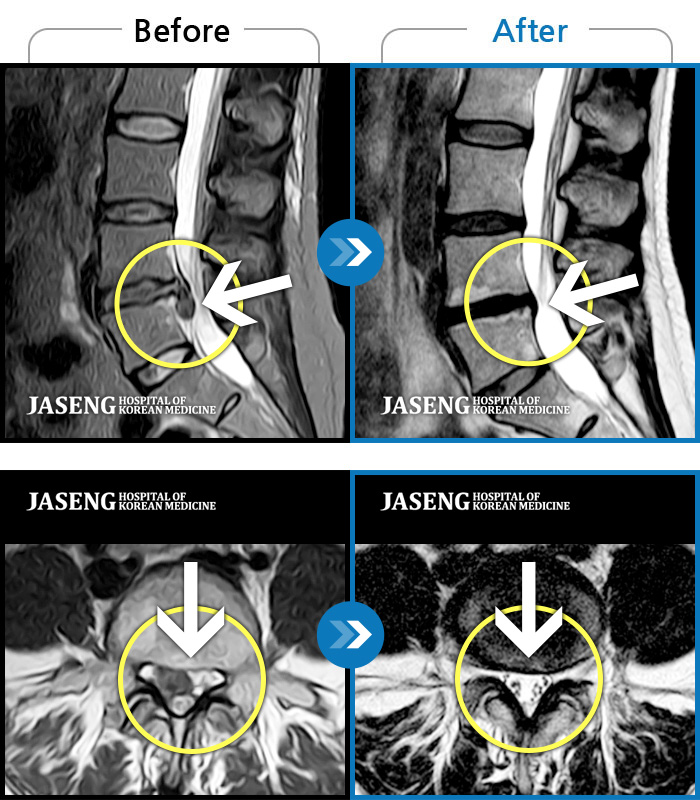

Before

After

환자에게 사전 동의를 받아 동일 조건에서 촬영되었습니다.

개인에 따라 치료 후 부작용이 발생할 수 있으니 의료진과 상담 후 치료를 진행하시기 바랍니다.

좌측 다리 저림이 매우 심해 야간통증 및 일상 생활에 제한이 많은 상태로 내원하였습니다.

허리 통증과 우측 허벅지 통증 및 저림 증상 지속되어 내원하셨습니다.